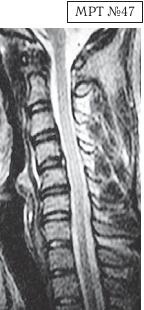

На МРТ № 47 наблюдается сглаженность лордоза с незначительной кифотизацией, которая привела к абсолютному стенозу спинномозгового канала и блоку ликворных путей, а также протрузии в сегменте СIV-СV, вентральному спондилёзу в сегменте CV-CVI и остеофитозу в сегменте CVI-CVII, гипертрофии передней и задней продольных связок. Это наиболее значительные проблемы в данном отделе. ![]() На МРТ № 48 наблюдается сглаженность лордоза, но без кифотической деформации, снижение высоты межпозвонковых дисков, протрузии в сегментах CV-CVI и CVI-CVII, частично компенсированные спондилёзом, выражены краевые остеофиты на данном уровне, абсолютный стеноз и блок ликворных путей, гипертрофия передней и задней продольных связок. ![]() На МРТ № 49 наблюдается кифоз шейного отдела позвоночника, хотя он и не привёл к абсолютному стенозу спинномозгового канала позвоночника, однако значительно нарушил ликвородинамику. Вентральное эпидуральное пространство блокировано вершиной кифоза с экскавацией и оттеснением спинного мозга, а дорсальное эпидуральное пространство блокируется чуть ниже от вершины задней стенкой спинномозгового канала. МРТ № 50